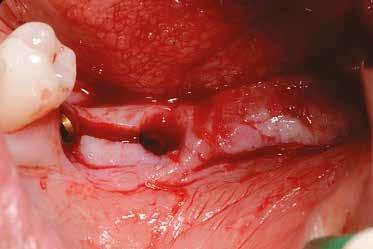

1. ábra: A műtét előtti szituáció, megfigyelhető az implantátumok közötti konkáv terület, ahova könnyen beragad az ételmaradék, és könnyen kialakul a periimplantitis.

Egy 47 éves páciens jelentkezett nálunk egy alsó, hátsó foghiánnyal, ahol jelentős csontfelszívódást tapasztaltunk a moláris fogak korábbi eltávolítása miatt (1. ábra). Két implantátum körül is volt ínyrecesszió, illetve a keratinizált íny mennyisége minimális volt (kevesebb, mint 1 mm). 4 hónappal az implantációt követően ínykorrekciót végeztünk.

Helyi érzéstelenítést végeztünk a műtéti területen artikain és 1:100 000 adrenalin segítségével. A recipiens területet előkészítettük, élesen disszekciót végeztünk, hogy egy izomtapadástól mentes periosteum ágyat képezhessünk. Ettől disztálisan két párhuzamos parakresztális metszést végeztünk egy 15C-s szikepengével, majd a metszéseket egy

2–5. ábra: A metszések és a deepitelizáció. – 6–9. ábra: Félvastag lebeny. – 10. ábra: A nyelezett ínylebeny „bepróbálása”.

horizontális metszéssel kötöttük össze (2–5. ábra). A metszések hosszát és a köztük lévő távolságot minden esetben a lágyszövet augmentációhoz szükséges keratinizált szövet határozza meg. A lebeny deepitelizációját egy 15C-s szikepengével végeztük (6. ábra). Ezt követően félvastag lebenyt preparáltunk (7. ábra). A lebenyt apikálisan, az alapjáról belső, felületes metszéssel felszabadítottuk, hogy passzívan áthelyezhessük és rögzíthessük, feszülés nélkül. Meziális irányba 180 fokkal átforgattuk (8–9. ábra). A meziális papillát alagúttechnikával (tunnelling technique) készítettük elő a graft befogadására (10. ábra). Az így kialakított lebenyt a recipiens ágyban rögzítettük az újonnan kialakított vesztibulum alapjánál 5-0 nem felszívódó PTFE (Coreflon, IMPLACORE) varratokkal. A graftot behajtottuk az ínyszél alá és meziális oldalon rögzítettük PTFE varratokkal (11–14. ábra)